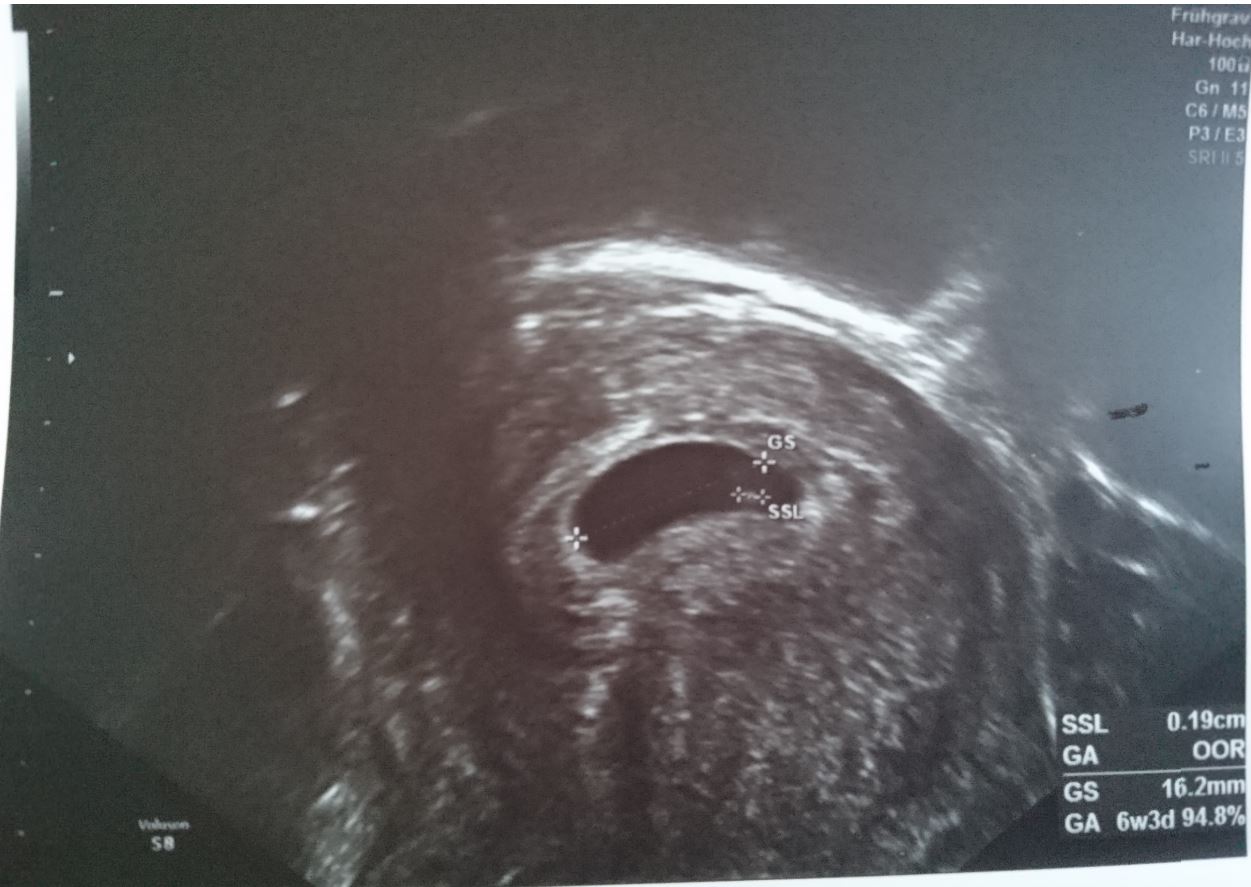

The first picture is taken in 6 wk, the secon 9 wk - both transvaginal.

Attachment 41073Attachment 41074Attachment 41072